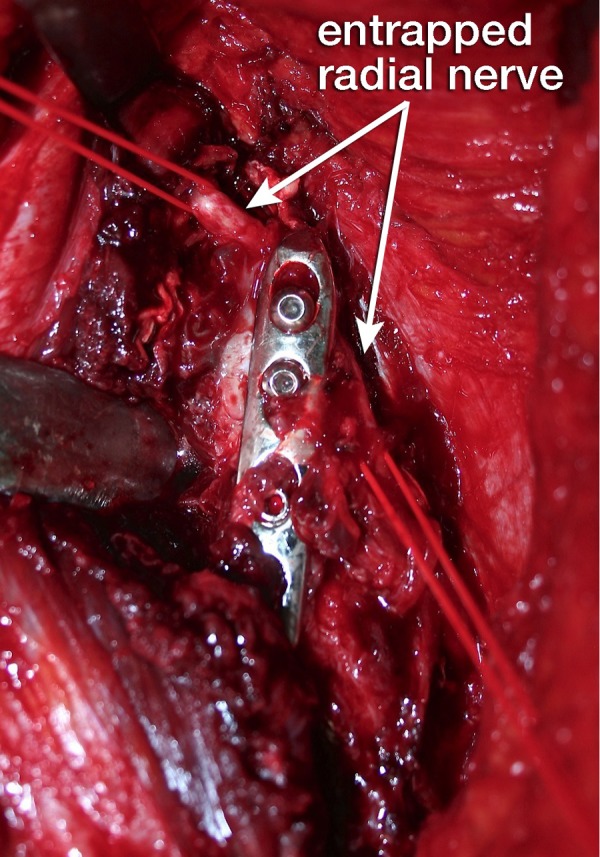

We decided to perform a radial nerve exploration and revision fixation using a double plating technique. We used a modified posterior approach of the humerus according to Gerwin et al.5 Intraoperatively, the radial nerve was found entrapped under the fixation plate. Locking screws were used but the plate was snugged down to the bone. After removing the plate, the nerve appeared to have been crushed by the plate and in addition the proximal screw had skewered and partially transected the nerve for at least 40% of its diameter (figure 4). Based on these devastating intraoperative findings, we believed the nerve to be irreversibly damaged. Even so, an external neurolysis was performed. The partially transected part was repaired with end-to-end neurorrhaphy using Ethilon 9.0 sutures under surgical microscope magnification (figure 5).

Figure 4.

Radial nerve (marked by red vessel loops) partially crushed between the locking plate and the humerus.